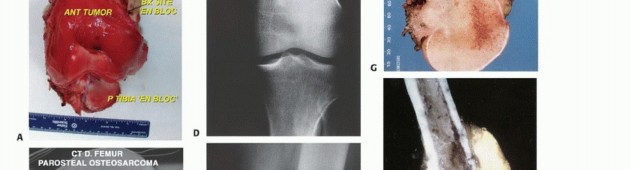

* Surface: Parosteal/Periosteal osteosarcoma.

- Plain Radiography: The cornerstone of initial evaluation. It accurately predicts the diagnosis in over 80% of extremity bone tumors. It defines the lesion's location, zone of transition (narrow/sclerotic = benign/slow; wide/permeative = malignant/aggressive), cortical destruction, and periosteal reactions (Codman triangle, onion-skinning, sunburst pattern).

- Computed Tomography (CT): The modality of choice for assessing fine osseous detail, cortical integrity, and matrix mineralization. Thin-slice (≤1 mm) helical CT allows for precise 3D reconstructions. Intravenous contrast is essential to delineate the relationship of the soft tissue mass to major vascular bundles. Chest CT is mandatory for staging to rule out pulmonary metastases.

- Magnetic Resonance Imaging (MRI): The gold standard for evaluating the local extent of the tumor. It accurately defines the intramedullary extent (allowing calculation of bone resection levels), soft tissue extension, joint involvement, and the presence of skip metastases. T1-weighted images best define marrow replacement; T2-weighted and STIR sequences highlight peritumoral edema and the soft tissue mass. Contrast enhancement differentiates cystic from solid components and clarifies neurovascular proximity.

Biopsy is the final, definitive step in staging. It must be meticulously planned by the treating orthopedic oncologist. Poorly executed biopsies can contaminate tissue planes, necessitating amputation instead of limb salvage. Core needle biopsy is preferred; if open incisional biopsy is required, it must be longitudinal, meticulously hemostatic, and placed entirely within the planned definitive resection tract.